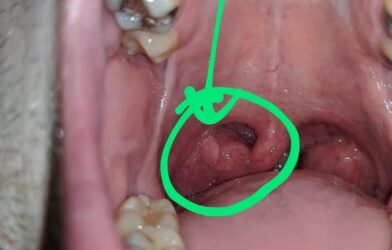

Le plaisir pourrait-il avoir un prix si élevé ? Une récente étude vient de révéler un lien inquiétant entre les pratiques sexuelles orales et le développement de cancers de la gorge. En effet, les chercheurs ont découvert que les personnes ayant eu de nombreux partenaires sexuels et pratiquants régulièrement la fellation ou le cunnilingus sont huit fois et demie plus susceptibles de développer ce type de tumeur. À l’origine de cette augmentation drastique du risque : l’infection par le papillomavirus humain (HPV). Ce virus, déjà connu pour provoquer des cancers du col de l’utérus chez la femme, se transmet facilement lors des rapports bucco-génitaux. Les chercheurs ont établi un lien direct entre la présence de l’HPV dans la bouche et l’apparition de tumeurs au niveau de la gorge.

Une étude alarmante menée par l’oncologue Maura Gillison vient de mettre en lumière un lien direct entre le nombre de partenaires sexuels, les pratiques de fellation et de cunnilingus, et le développement d’un certain type de cancer de la gorge. Les personnes ayant eu plus de 6 partenaires sexuels verraient leur risque multiplié par 8,6 ! Le principal auteur de l’étude, Maura Gillison se veut néanmoins rassurante : « le public devrait cependant être rassuré car le cancer oropharyngé est relativement rare et la grande majorité des personnes ayant une infection orale par papillomavirus ne développeront pas de cancer ». Cette étude permet de rappeler que le sexe oral n’est pas dénué de risques et peut être un mode de transmission de maladies sexuellement transmissibles.

La muqueuse de la bouche est particulièrement vulnérable aux infections virales. De plus, l’HPV peut persister dans l’organisme pendant de nombreuses années avant de provoquer l’apparition d’un cancer. C’est pourquoi il est important de consulter régulièrement un médecin pour dépister d’éventuelles lésions précancéreuses. Les symptômes du cancer de la gorge peuvent être discrets au début et souvent confondus avec ceux d’un simple rhume. Parmi les signes les plus courants, on retrouve : Des maux de gorge persistants, un enrouement inexpliqué, des difficultés à avaler, des douleurs à l’oreille et une masse dans le cou.